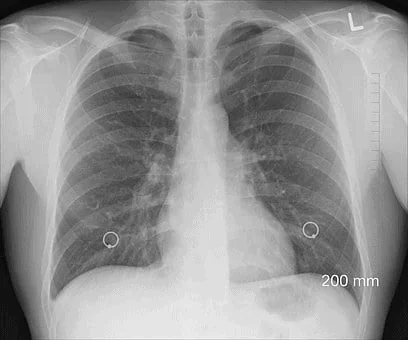

Pulmonary contusion is a condition resulting from trauma or a direct blow to the chest. The condition mainly emanates from car crashes or falls. Victims who sustain these injuries have a difficult time moving on with their regular life. Some of the common symptoms to look for after a car accident include:

When force is applied to the lungs, blood vessels get damaged. Victims who experience chest injuries mostly develop pulmonary contusion. When such a condition is left unchecked, this can lead to life-threatening consequences.

One way to secure a favorable settlement or judgment is to seek medical help immediately. This will allow you to confirm that you suffered injuries after the accident. Lung contusion can result from chest trauma following a high energy braking or deceleration. In some instances, the victim may develop lung contusion without single tissue damage in the chest.